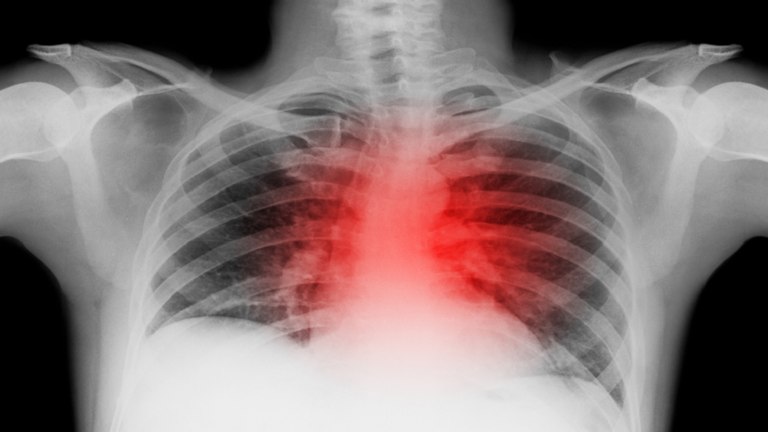

تعرف عليها.. 5 نصائح لتقليل خطر إصابتك بهذه الحالة التي تهدد حياتك!